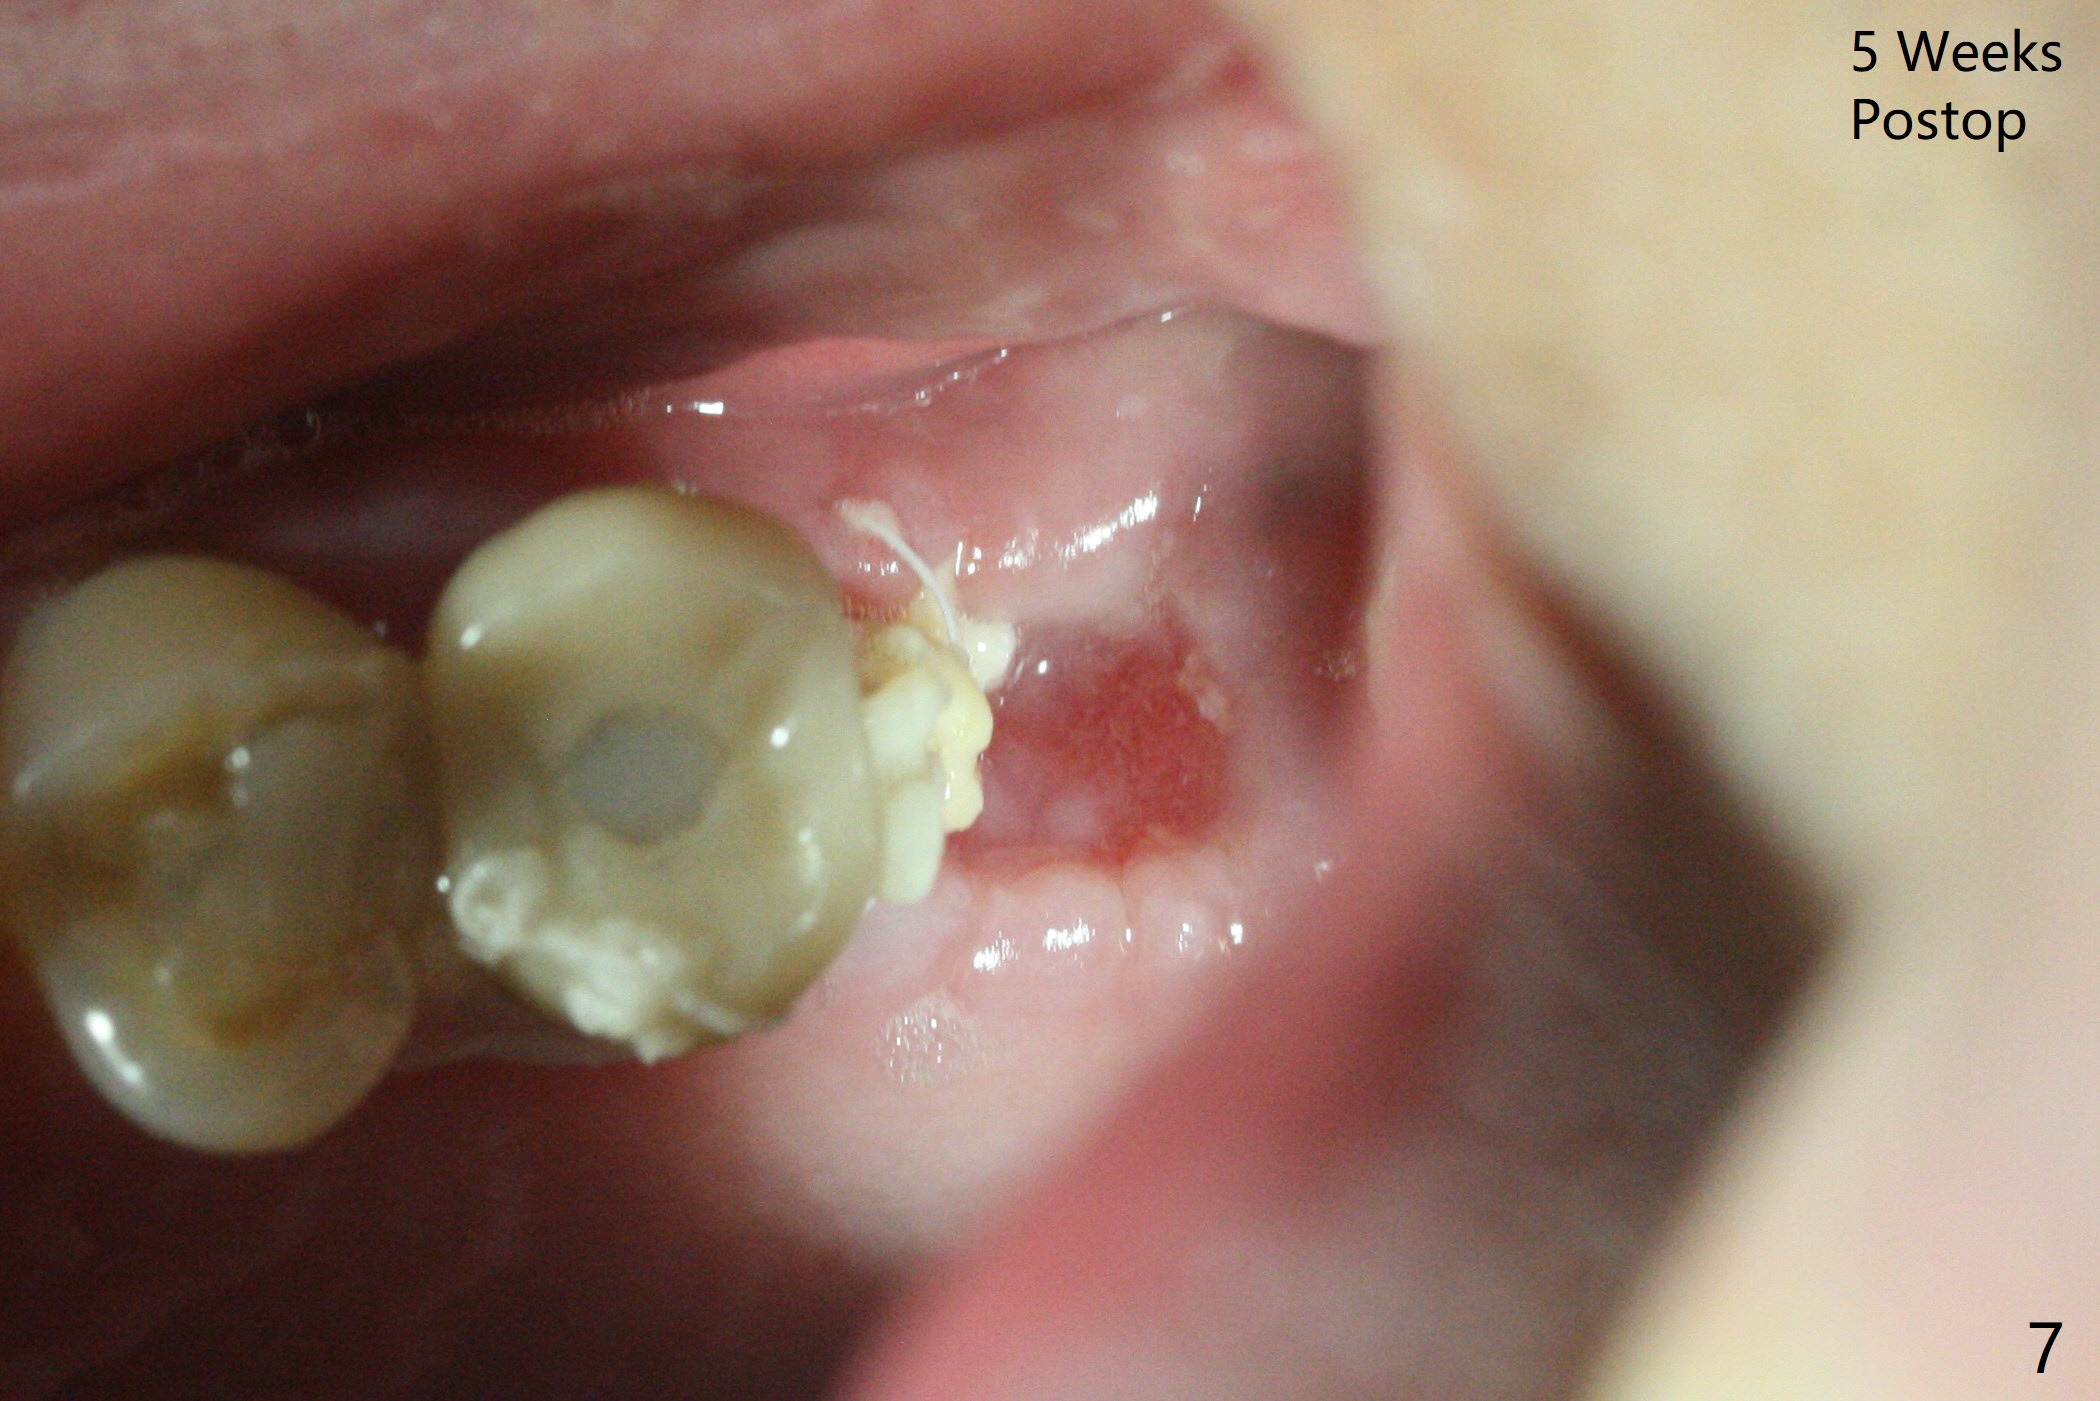

左上六拔除后,近中颊侧窝尤其大,与上颌窦相通(图一 *),而中隔比较尖,截除后还显得窄(图一,二:S),不太适合即刻种植。放置一块PRF膜于近中颊侧窝修补上颌窦,然后放置粘性骨块,好像有上颌窦提升迹象(图三:*(箭头:近中颊侧骨板缺失)),用骨粉填满其余牙槽窝(图四),覆盖另外一块PRF膜以及Cytoplast(不可吸收膜),用PTFE缝线(也不可吸收,与膜是同一个材料,非常柔软,好打结)缝合(图五)。最后使用牙周敷料。后者术后八九天脱落,病人术后十二天复诊,不可吸收膜腭侧有些外翻(图六箭头),伤口愈合尚可,没有骨粉丢失迹象,反复交代口腔卫生。再过三周撤除不可吸收膜。其实三周后膜自己脱落,病人回来撤去剩余缝线(图七),新鲜肉芽组织形成。术后5个月牙槽嵴和角化龈宽,骨高度尚可(图八),密度差些(图九,750单位),植体应该是4.5x8.5 或者 10 毫米,少量上颌窦提升。